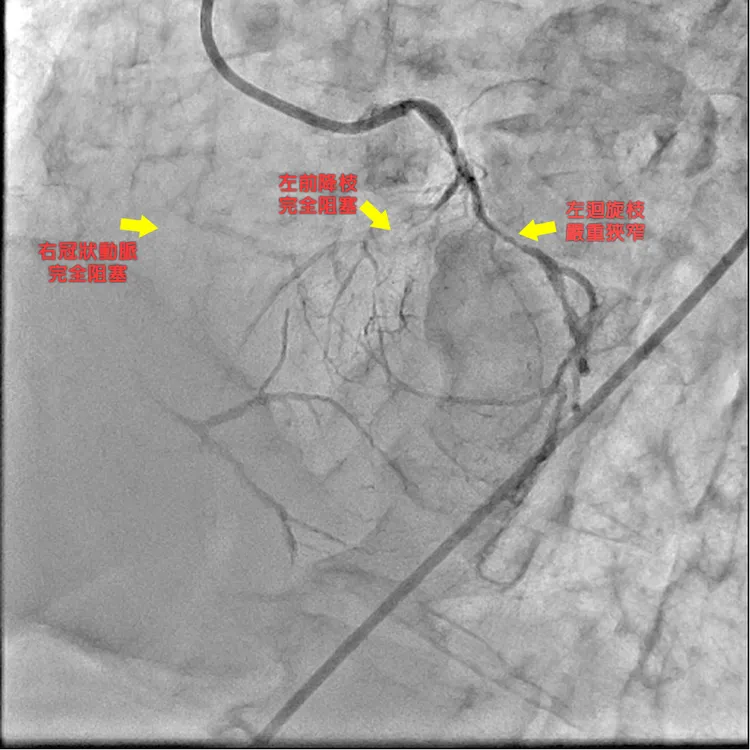

中港澄清醫院心臟心管內科醫師孫德光表示,這名患者發病前出現上腹陣痛、噁心想吐,以為是急性胃炎,服用胃藥但毫無緩解,卻在工作中因呼吸困難全身無力而被送進急診,檢查發現他心臟3條冠狀動脈血管有2條呈現完全阻塞,一條嚴重狹窄,且左主幹也呈現重度狹窄,其心臟功能射血指數僅22%(正常為50%以上),顯示已出現嚴重心臟衰竭,隨時危及生命,立即給予呼吸器支持。

醫療團隊考量患者經濟負擔、短中長期之治療效果以及預後考量,最後決定不做心導管支架置放手術,緊急會診心臟外科為病患進行心臟血管繞道手術,這樣對患者的經濟負擔最輕,將治療的長期效益最大化,該患者於手術住院10天後順利出院。